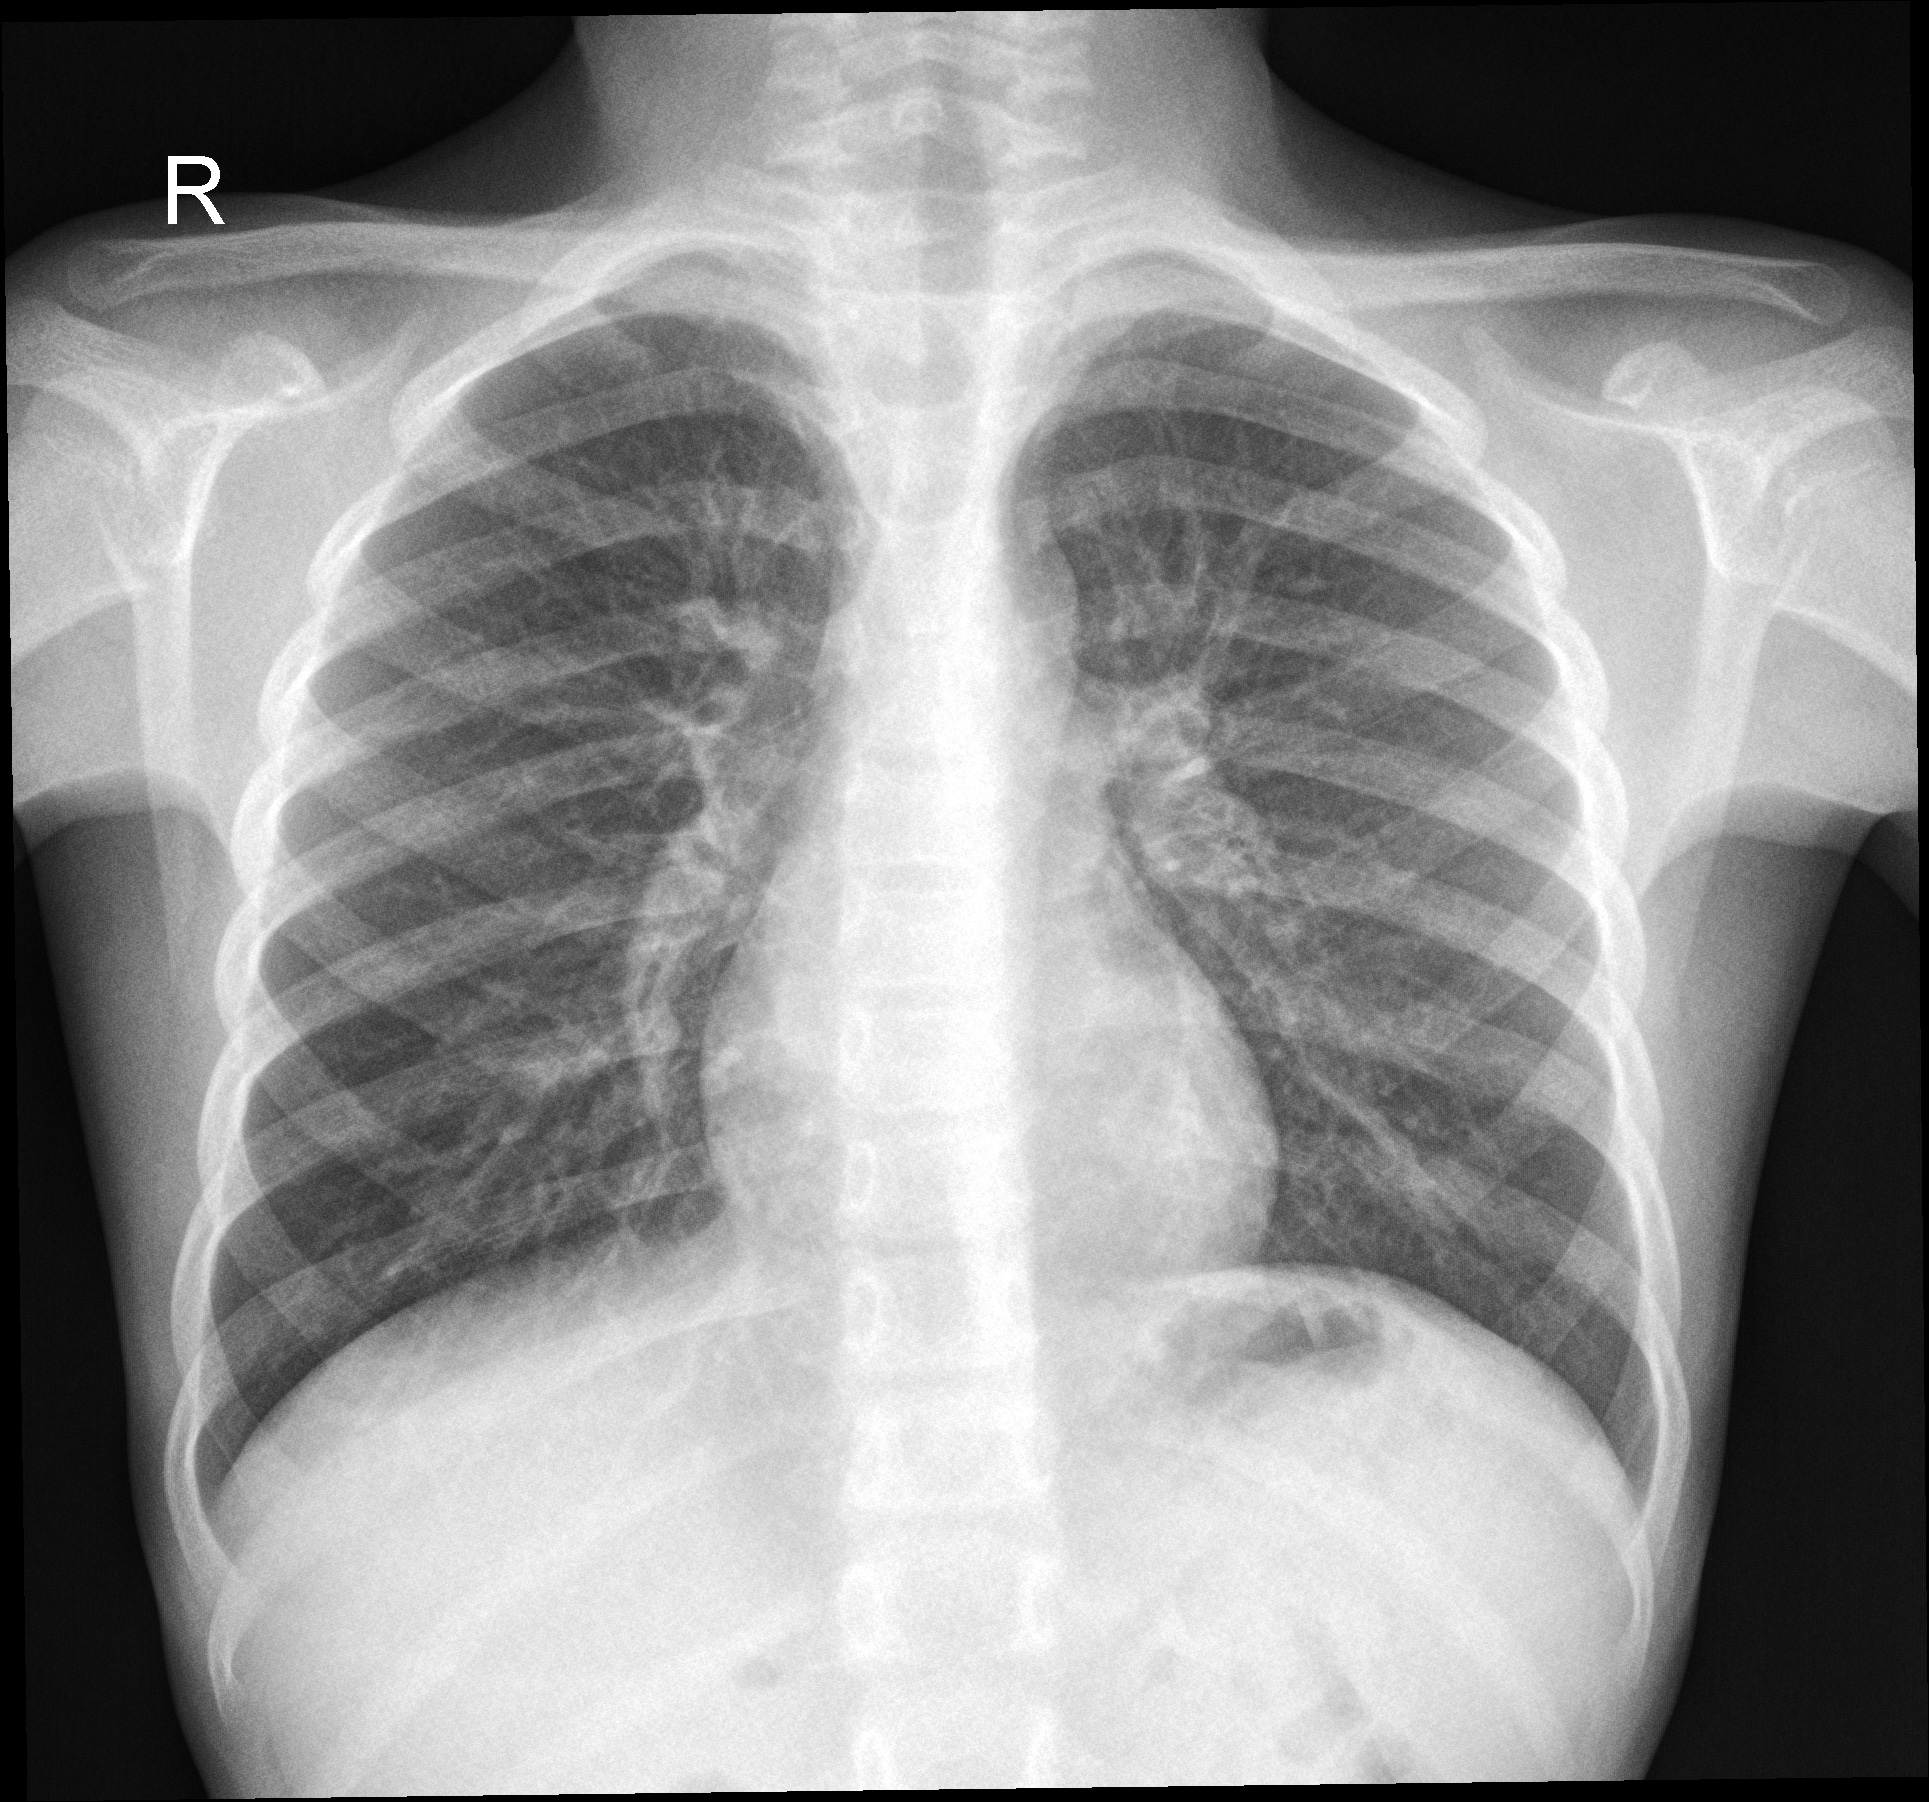

(c) Lungs of a chlamydia infected patient.

Figure 1: Examples of PA chest X-rays in the data-set in Figures 1(a) to 1(d), and distribution of the diagnoses based on the PA chest X-rays in Figure 1(e).